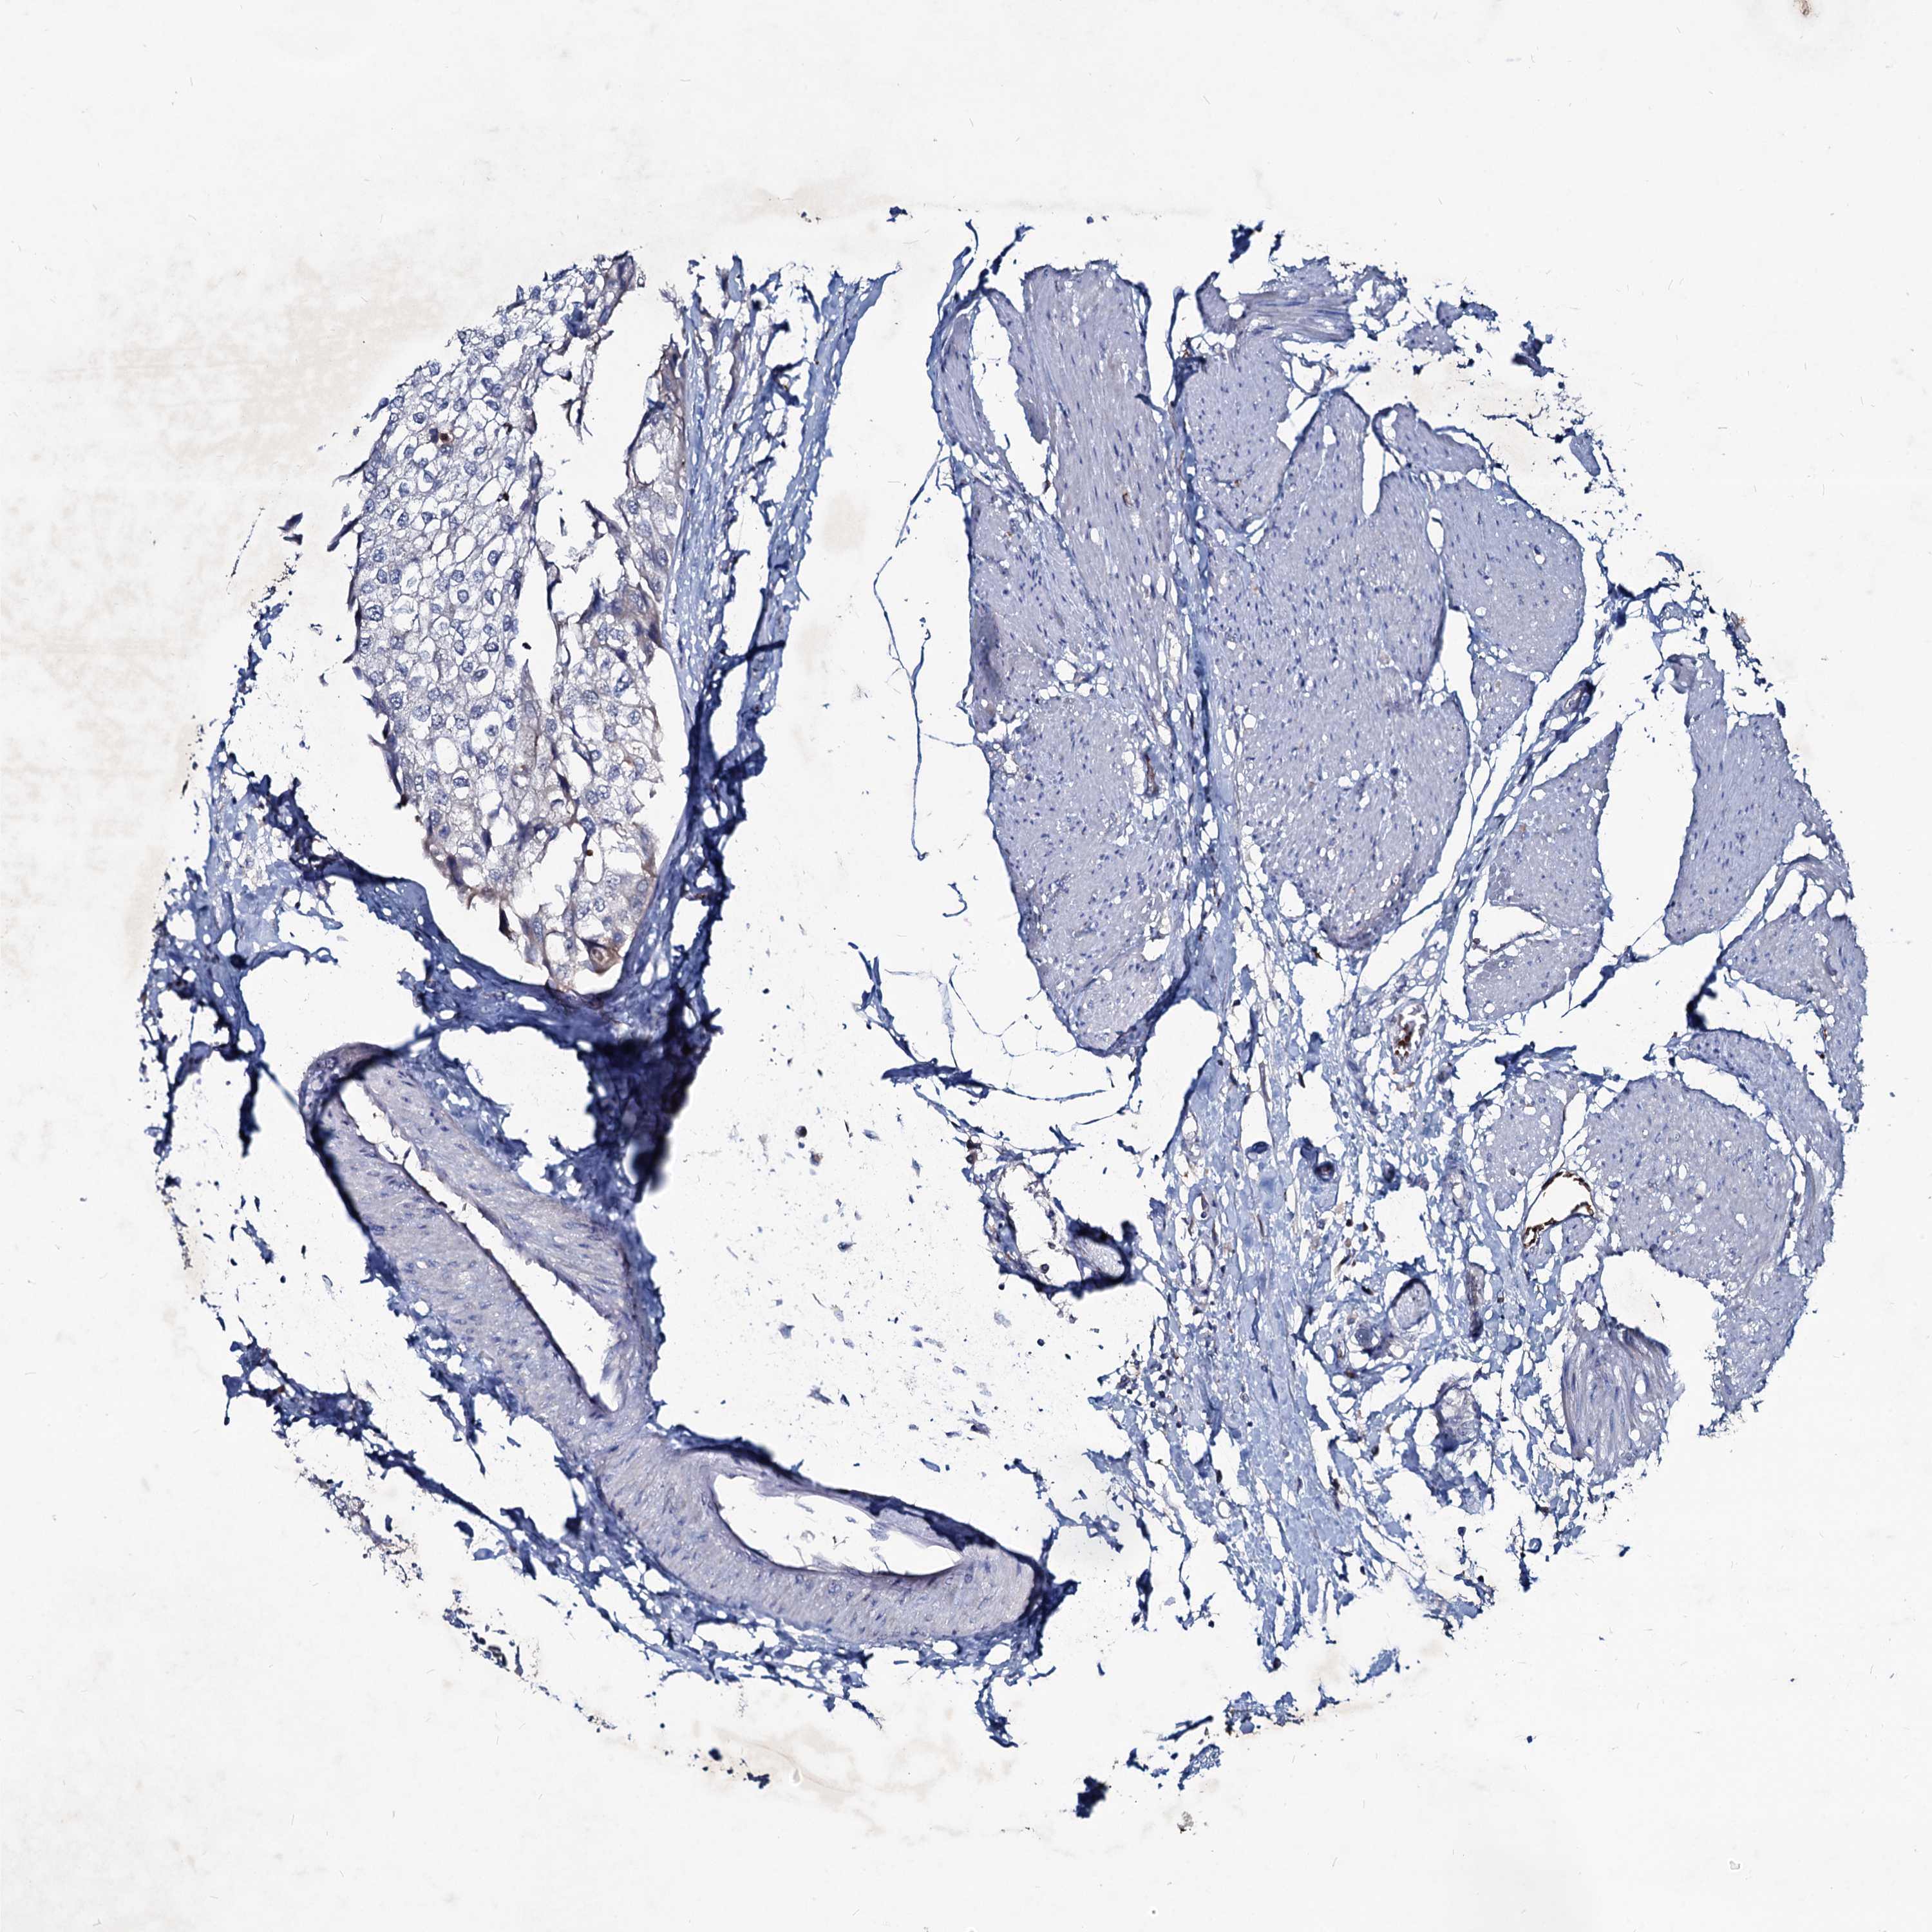

UROTHELIAL CANCER - Protein expressioni

A mouse-over function shows sample information and annotation data. Click on an image to view it in a full screen mode. Samples can be filtered based on level of antibody staining by selecting one or several of the following categories: high, medium, low and not detected. The assay and annotation is described here.

Note that samples used for immunohistochemistry by the Human Protein Atlas do not correspond to samples in the TCGA dataset.

Antibody stainingi

Antibody staining in the annotated cell types in the current human tissue is reported as not detected, low, medium, or high, based on conventional immunohistochemistry profiling in selected tissues. This score is based on the combination of the staining intensity and fraction of stained cells.

Each image is clickable and will lead to virtual microscopy that enables deeper exploration of all samples and also displays staining intensity scores, fraction scores and subcellular localization as well as patient and tissue information for each sample.

Antibody HPA039343

Antibody HPA040048

Urothelial carcinoma, High grade

Urothelial carcinoma, Low grade